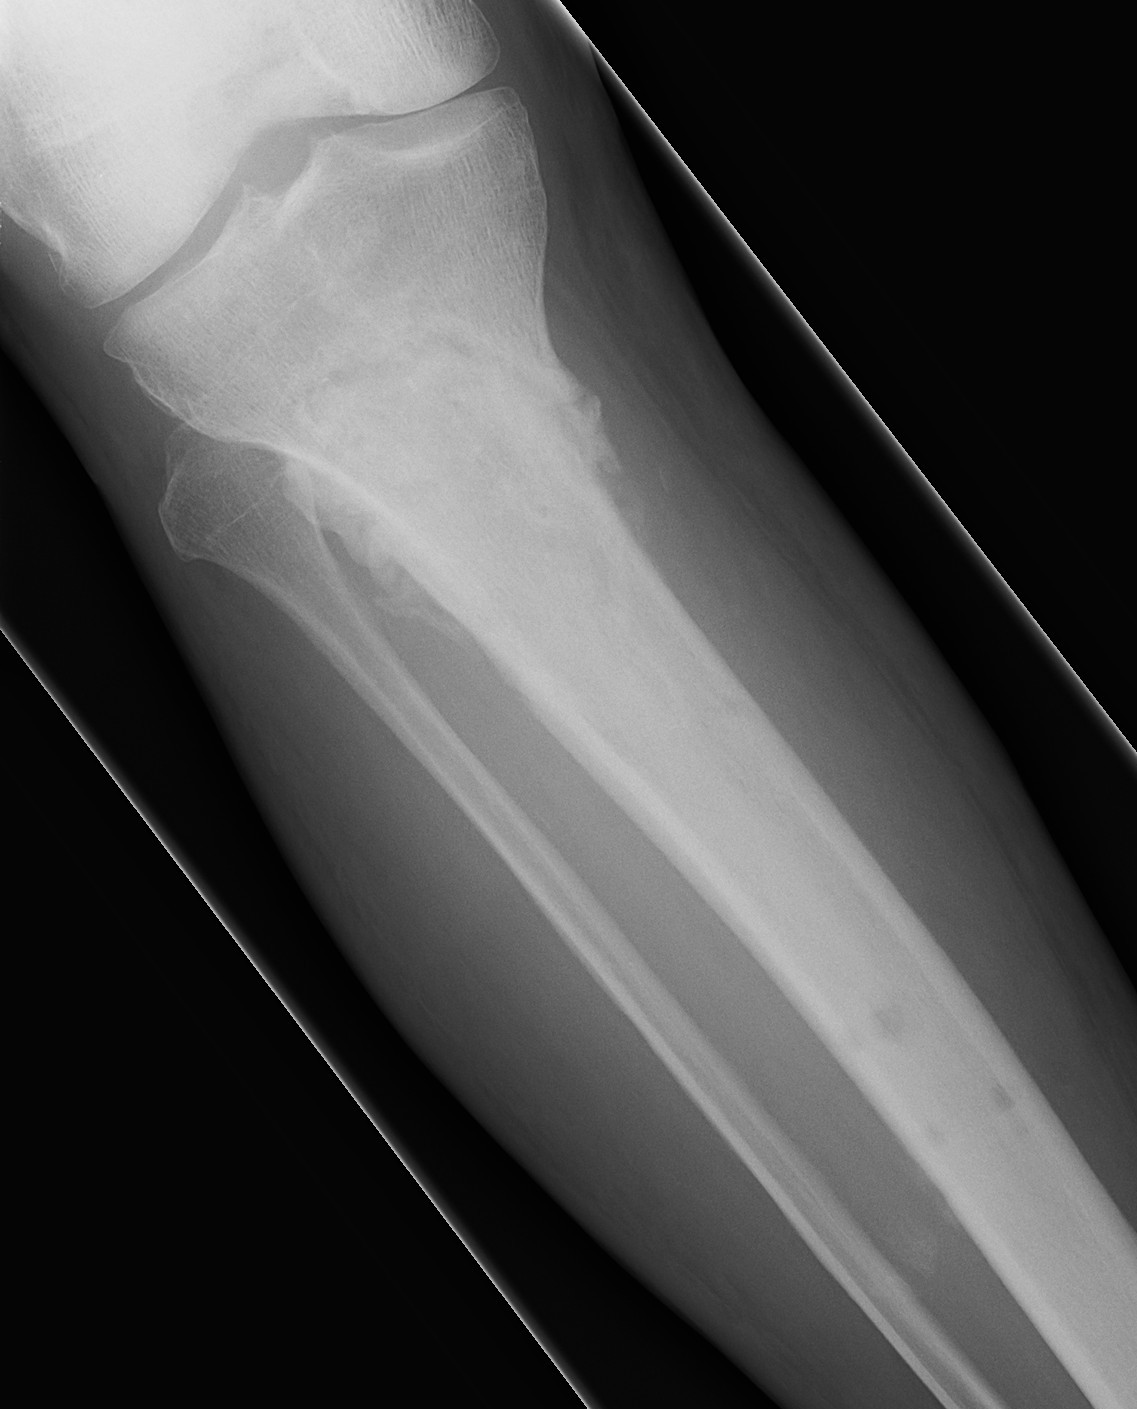

AP View Angulation + Translation

Lateral View Angulation + Translation

Axial Translation (Shortening)

Axial View Angulation

Set Origin / Corresponding Point on AP and Lateral

Origin

- reference fragment

Corresponding point

- on moving fragment